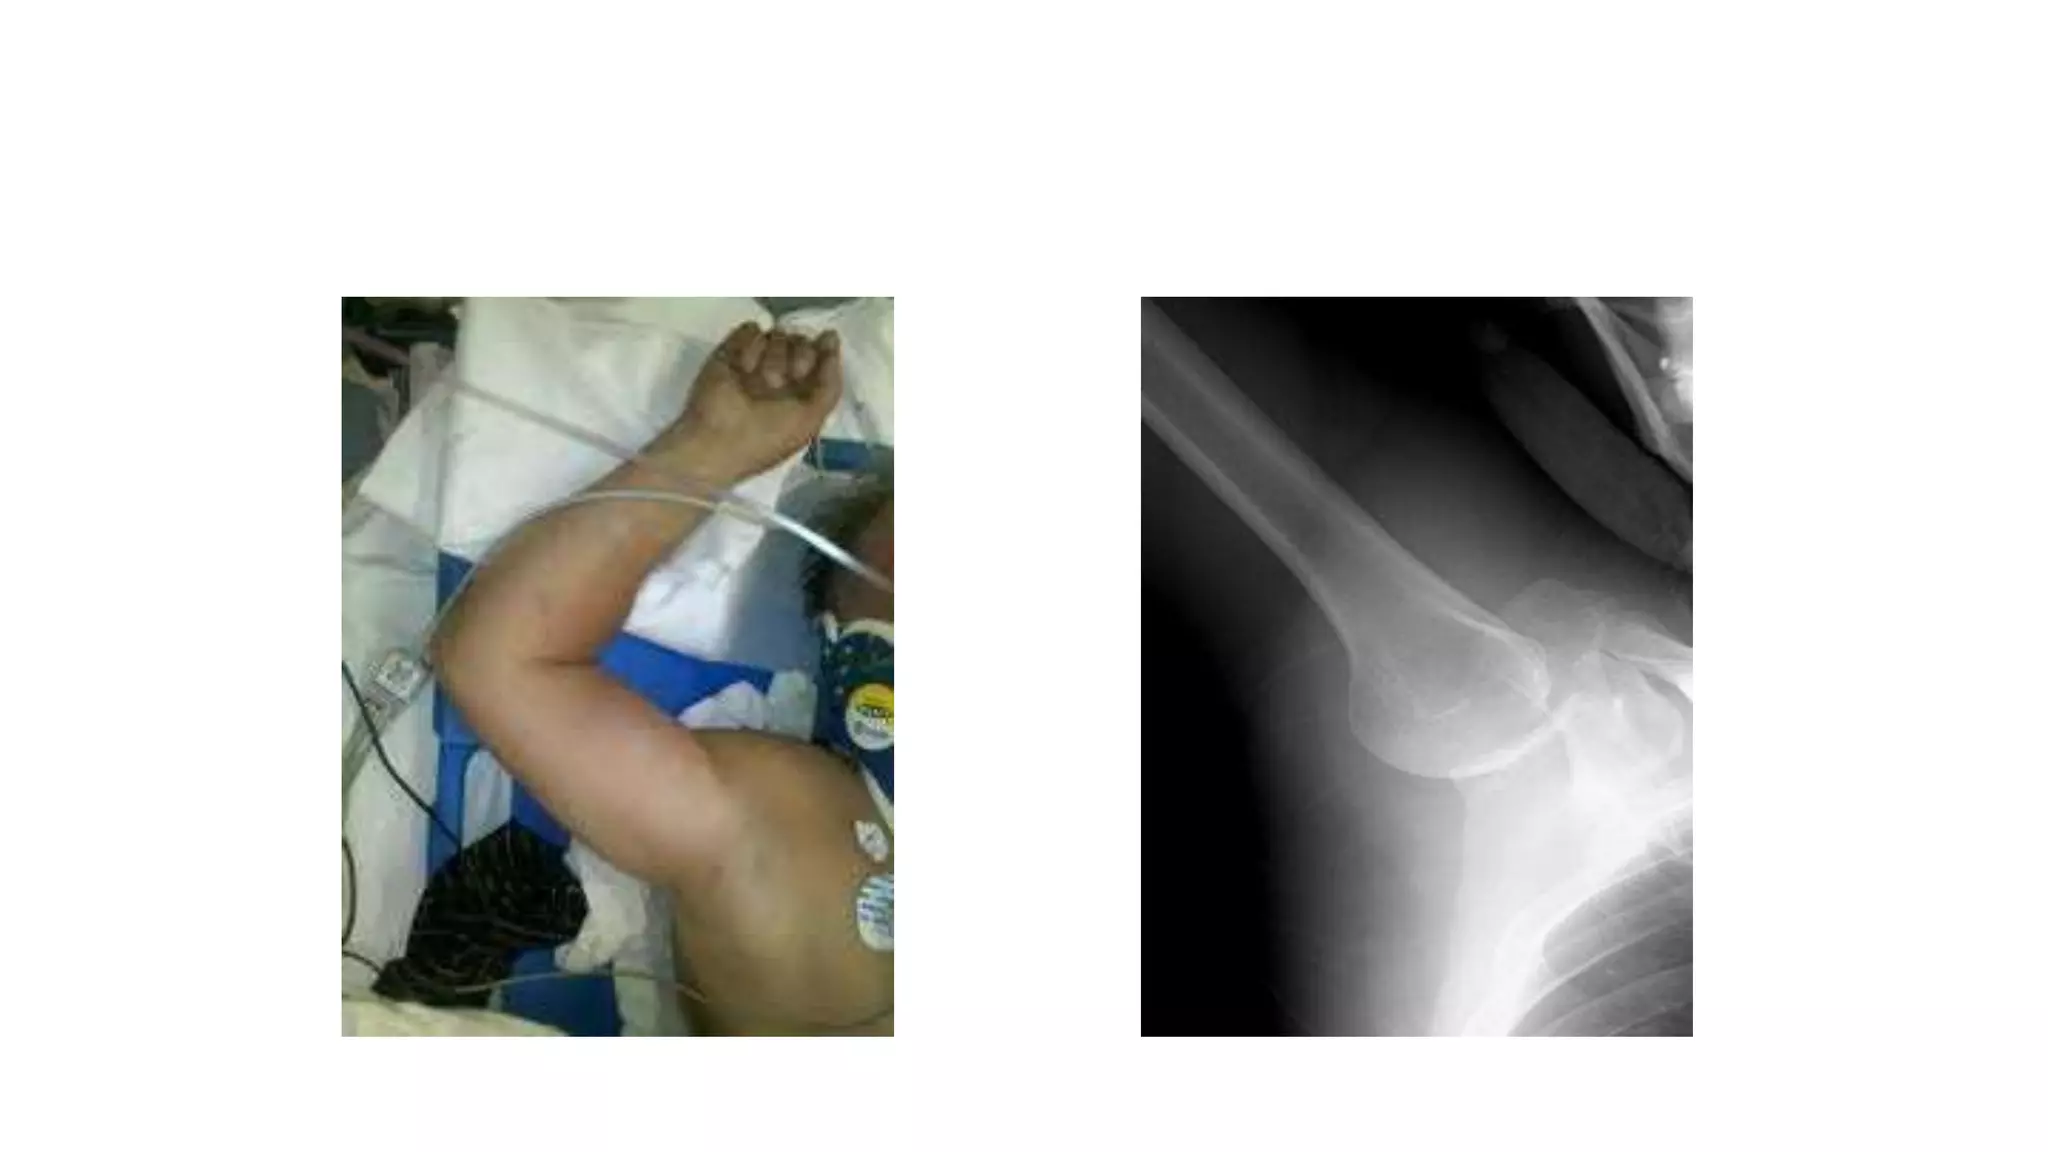

Clinical Picture

• Pain

• Holds injured limb with other hand close to trunk

• The shoulder is abducted and the elbow is kept

flexed

• Loss of the normal contour of the shoulder

• Anterior bulge of head of humerus may be visible

or palpable

• Empty glenoid socket

Diagnosis

• A shoulder dislocation is diagnosed clinically when

significant pain, alterations in the appearance of

the shoulder anatomy and impaired movement of

the shoulder are present.

• Standard X-ray of the shoulder forms the first

diagnostic approach to confirm the type of

humeral head displacement and potentially

associated injuries to the surrounding bones.

Anterior Dislocation

◦ 97% of recurrent dislocations

◦ It is the most common dislocation

◦ cause inability to abduct the arm.

◦ loss in the round contour of the

shoulder.

◦ The most severe cases of anterior

dislocation of the shoulder are

associated with injury to the axillary

artery and the axillary nerve.

Anterior Dislocation of Shoulder

Shoulder APview

Shoulder PA or Scapular Y-view